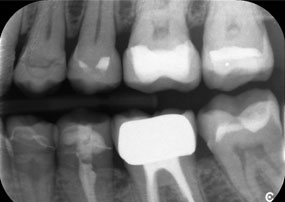

Otro ejemplo del rendimiento clínico de Power Edition fue la sustitución de una corona de zirconio dañada en una paciente de 63 años. El daño se produjo debido a la rotura de una parte del revestimiento de la corona de zirconio de 20 años de antigüedad en el diente 6. A pesar de encontrarse en la zona posterior, a la paciente le molestaba y deseaba una nueva corona.